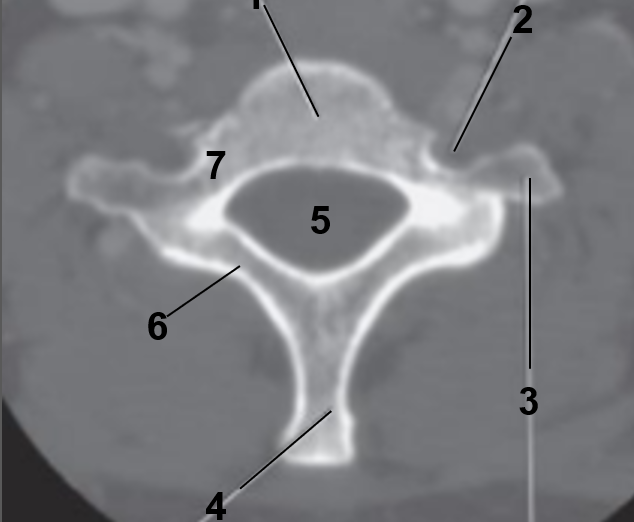

1

Transverse foramen

2

Anterior arch

3

Transverse Process

4

Posterior arch

5

Superior articular facet

6

Dens

7

Vertebral Foramen